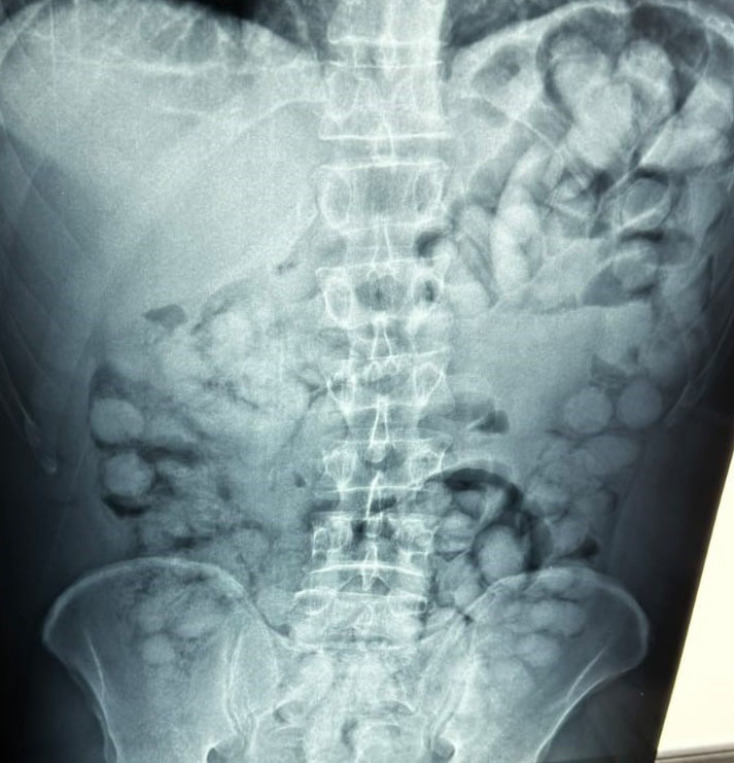

Ο άνδρας που ταξίδευε από Βραζιλία μέσω Γαλλίας, είχε καταπιεί 100 συσκευασίες κοκαΐνης. Η κάθε συσκευασία ήταν 10 γραμμαρίων και καθαρότητας 90%.